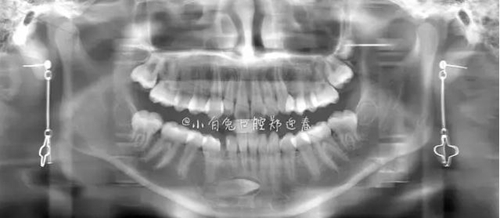

本案:患兒,女,14歲,因牙齒矯正來院,檢查見83滯留,43未見萌出,拍片發(fā)現(xiàn):43埋伏阻生于31、41、42根尖下方,按照正畸診療計(jì)劃,擬行43拔除術(shù)。

全景片